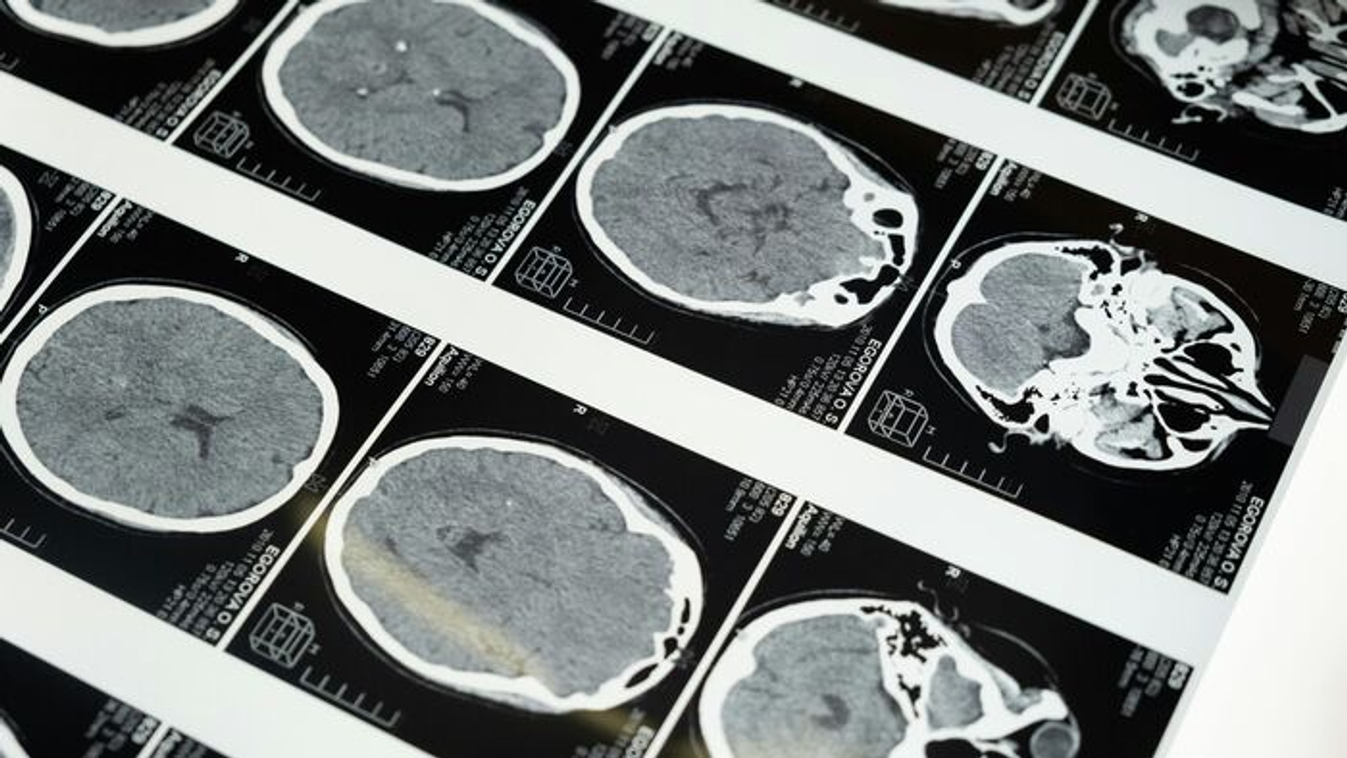

Elbagatellizálták a lány tüneteit - végül sokkoló diagnózist kapott egy súlyos tünet után

Egyik nap összeesett a mosdóban.